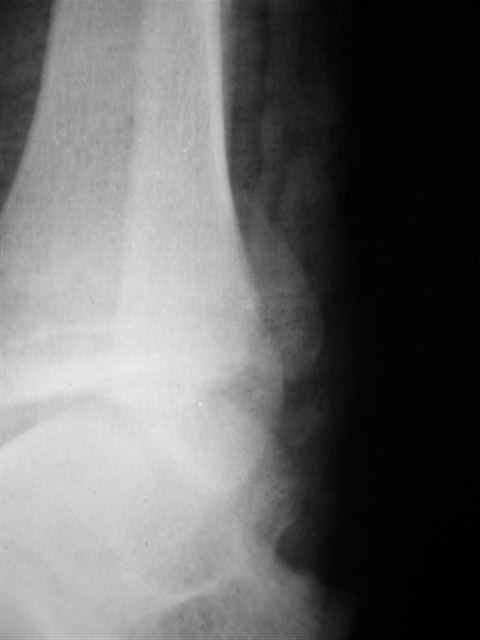

Я предупреждал, что ничего сверхъестественного. Каюсь, что одна из спиц прошла несколько дальше, чем нужно было, но главное - перелом стабилизирован и больной работает суставом в полном объёме, несмотря на представленную раннее травму коленного сустава.